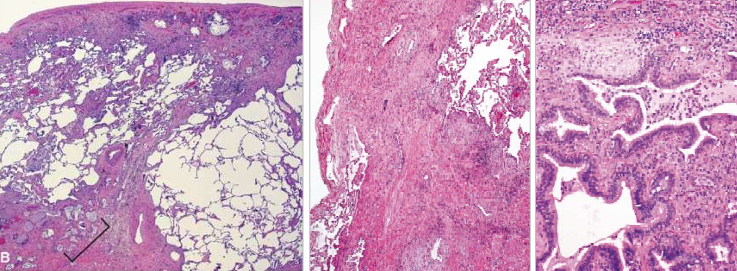

FPI: micro